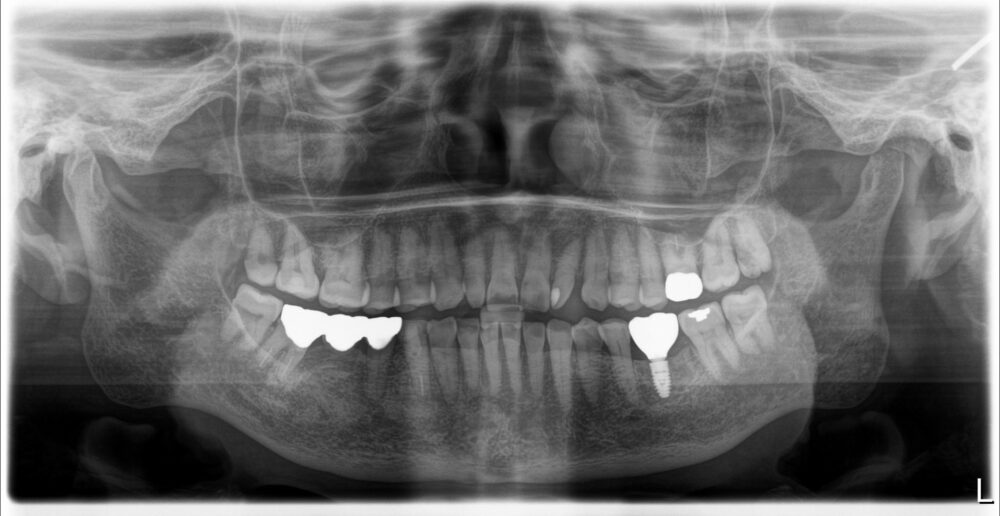

症例1

治療後

| 主訴 | 歯を入れたい |

| 診断 |

左下6残根 |

| 治療内容 | 左下6抜歯、インプラント補綴 |

| 年齢・性別 |

78歳、女性 |

| 治療期間 |

6ヶ月 |

| 治療費用 | 診査診断¥22000+インプラント一次オペ(京セラ)¥275000+GBR¥110000+上部構造(ジルコニア)¥143000 総額¥550000 |

| リスク・副作用 | インプラント周囲炎、インプラント上部構造の緩み |